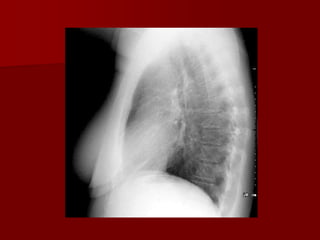

Lateral view

The only view that provides information of

localization of different lobes and segments

 Observation on lateral view include- clear

spaces, vertebral translucency , and outline of

diaphragms.